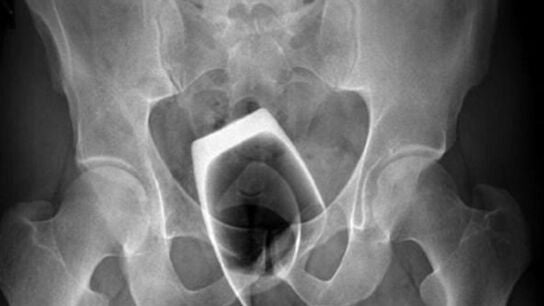

UNA PELIGROSA PRÁCTICA SEXUAL